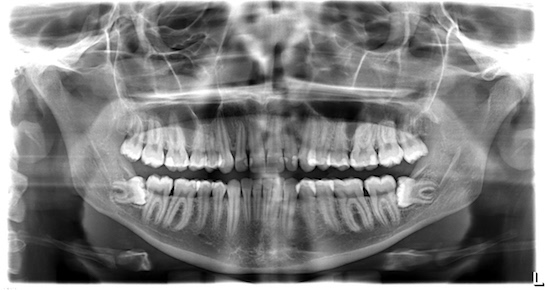

Heeft u ondanks de bovenstaande preventieve maatregelen, tóch nog pijnklachten? Neem dan contact op met de tandarts. De tandarts zal naar uw pijnklacht kijken en vervolgens een plan opstellen om de pijn te verhelpen. Let op: indien de pijn niet zichtbaar is, kunnen er mogelijk foto’s gemaakt worden. Deze foto’s laten de situatie van de niet zichtbare delen in uw mond zien, om te kijken of vanuit daar de pijnklacht opspeelt.